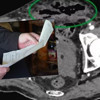

The Sun Gazetesi’nde yer alan habere göre, adama uygulanan BT taramasında çok sayıda gaz içeren apsenin genişleyen prostatında yer aldığı görüntülendi.